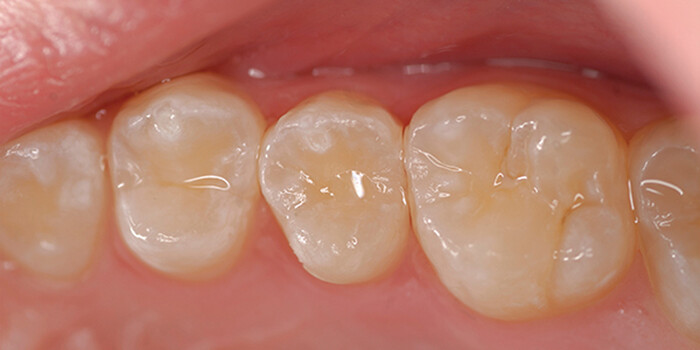

Стеклоиономерные реставрации у детских пациентов

Стеклоиономерные цементы (СИЦ) — это стоматологические пломбировочные материалы. Как сообщили в 1971 году Уилсон и Кент, ГИЦ не получили признания из-за низкой износостойкости и неспособности хорошо работать на боковых зубах.